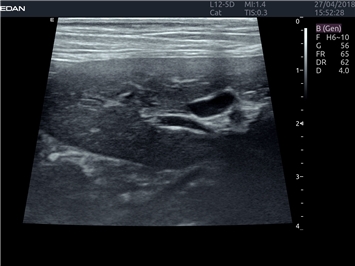

EDAN Acclarix LX4 VET представляет собой профессиональную ультразвуковую систему, специально разработанную для ветеринарных исследований. Сочетание стабильности, высокой производительности и эффективности делает эту систему идеальным выбором для современной ветеринарной практики.

• Универсальные датчики для различных видов животных

• Специализированные предустановки для ветеринарных исследований

B-режим, Двухмерное сканирование:

Да